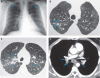

At that evaluation, a chest radiograph was performed (Figure 1A), and he was then referred to a chest clinic.

We performed thoracic

apex to base (Figure 1B–D).

The

lung are diffuse pulmonary nodules. Our case illustrates that on HRCT

these nodules are distributed along the bronchovascular bundles and can

coexist with mediastinal lymphadenopathy. In a study from Turkey (Kara et al. (2003),

a comparison of HRCT scans of 60 nonsmoking women with at least 10

years of biomass exposure with nonexposed controls showed significantly

more of the following abnormalities: reticulation, peribronchovascular

thickening, and nodular and ground glass opacities. The asymptomatic

subjects with exposure had significantly more ground-glass opacities

and less bronchiectasis than those with symptoms (Kara et al. 2003).

These data suggest that radiographic abnormalities are seen early in

the disease, even in asymptomatic or mildly symptomatic individuals,

and persist years after removal from exposure.

Figure 1

Chest radiograph (

A) and HRCT images (

B–D) of patient’s lungs. (

A)

Frontal chest radiograph showing mild symmetric linear and reticular

opacities (arrows) in the upper lobes bilaterally; these opacities are

associated with bilateral hilar

(more ...)